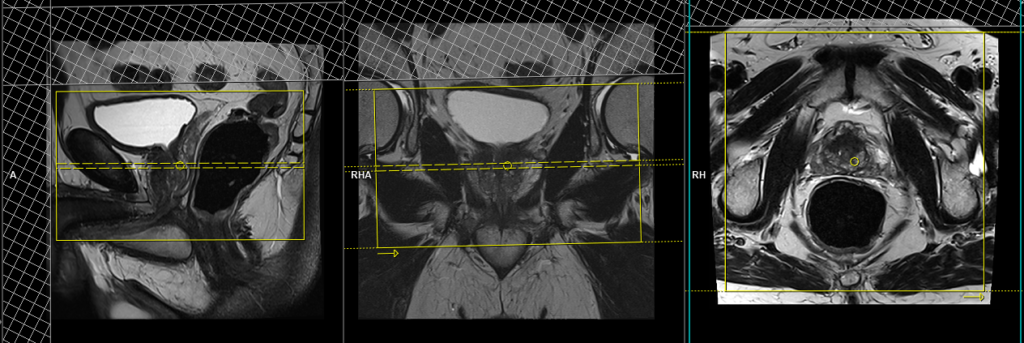

T2 tse axial 3mm SFOV prostate (straight axial)

Plan the axial slices on the sagittal plane; angle the positioning block horizontally across the prostate (i.e., parallel to the base of the penis). Check the positioning block in the other two planes. An appropriate angle must be given in the coronal plane (parallel to the right and left femoral heads). Slices must be sufficient to cover the whole prostate and seminal vesicles. Additionally, to minimize artifacts arising from arterial pulsation, peristalsis, and breathing, consider incorporating saturation bands on top and in front of the axial block.

Parameters

TR 4000-5000 | TE 100-120 | SLICE 3 MM | FLIP 130-160 | PHASE R>L | MATRIX 320X288 | FOV 180-200 | GAP 10% | NEX(AVRAGE) 4 |